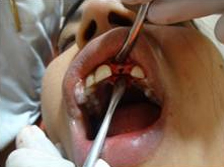

Use of Bone Graft & GTR membrane for an Implant

Pre Operation

Bone Graft in Extraction Socket